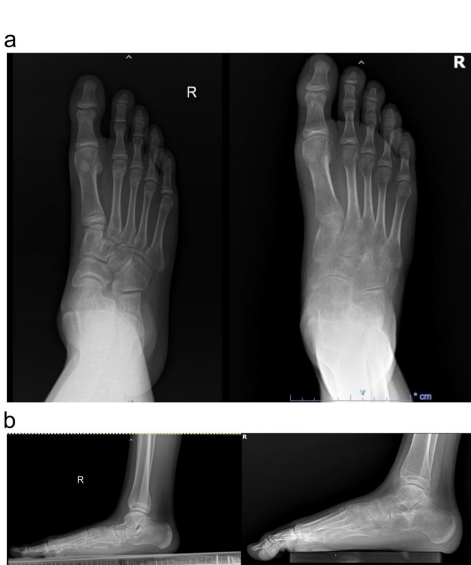

关键参数呈现两极分化改善:距跟角(TCA)减小5.48°、跟骰角(CCA)降低12.59°(均p<0.001),而跟骨倾斜角(CIA)和距骨覆盖率分别增加9.89°和10.23%,证实截骨术有效重建了足弓三维结构。典型病例影像显示(图1-3),术后距骨第1跖骨角(Meary's角)从平均6.85°显著改善。